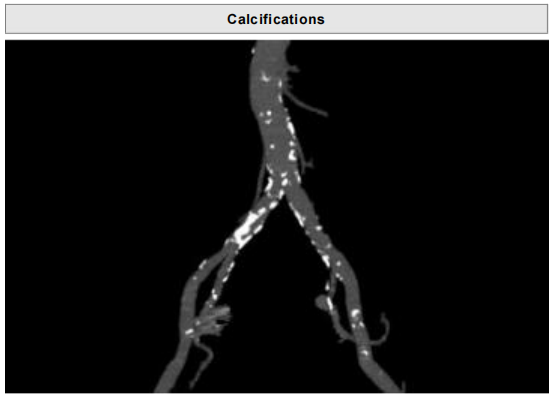

• 瓣叶钙化分布不均匀,右冠及无冠瓣叶可见明显钙化,瓣膜释放过程中存在移位风险。

• Type 1型二叶瓣,重度钙化,瓣叶钙化分布不均匀,瓣膜锚定难度高;

• 主动脉弓及腹主动脉、 髂总动脉可见明显钙化斑块,经股入路难度高;

超声心动图提示:主动脉瓣:主动脉瓣重度狭窄(Vmax=4.8m/s,PGmean=95mmHg);功能性二叶瓣,右无粘连;瓣叶轻度钙化;瓣下见中量反流。